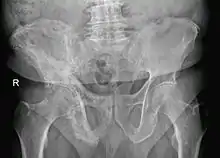

Paget's disease of right innominate bone. Man of 80 years age.